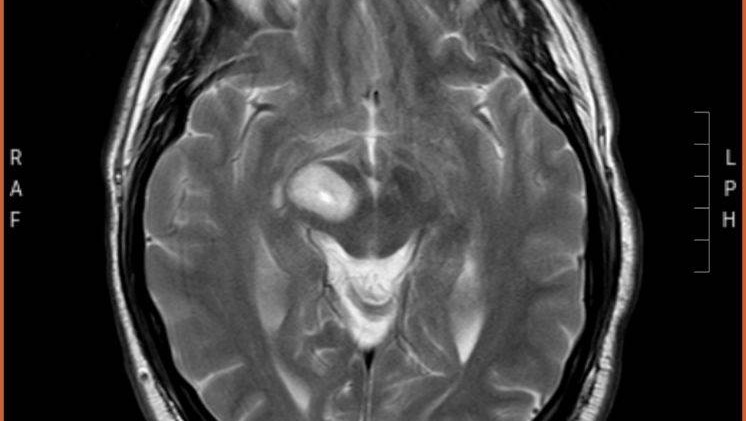

Here is a picture of the tumor, the egg shaped spot is it.